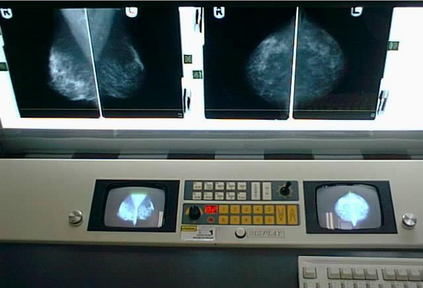

The need for AI systems to provide explanations for their behaviour is now widely recognised as key to their adoption. In this paper, we examine the problem of trustworthy AI and explore what delivering this means in practice, with a focus on healthcare applications. Work in this area typically treats trustworthy AI as a problem of Human-Computer Interaction involving the individual user and an AI system. However, we argue here that this overlooks the important part played by organisational accountability in how people reason about and trust AI in socio-technical settings. To illustrate the importance of organisational accountability, we present findings from ethnographic studies of breast cancer screening and cancer treatment planning in multidisciplinary team meetings to show how participants made themselves accountable both to each other and to the organisations of which they are members. We use these findings to enrich existing understandings of the requirements for trustworthy AI and to outline some candidate solutions to the problems of making AI accountable both to individual users and organisationally. We conclude by outlining the implications of this for future work on the development of trustworthy AI, including ways in which our proposed solutions may be re-used in different application settings.

翻译:现在人们普遍认为,需要AI系统对其行为作出解释,这是其通过的关键。在本文件中,我们研究了值得信赖的AI问题,并探讨了在实践中提供这种服务的实际意义,重点是卫生保健应用。这一领域的工作通常将值得信赖的AI视为涉及个人用户和AI系统的人-计算机互动问题。然而,我们在这里争辩说,这忽略了组织问责制在人们如何理解和信任AI在社会技术环境中所发挥的重要作用。为了说明组织问责制的重要性,我们在多学科小组会议上介绍了乳腺癌筛查和癌症治疗规划的人类学研究的结果,以表明参与者如何对彼此和他们所加入的组织负责。我们利用这些调查结果丰富目前对可信AI要求的理解,并概述一些备选解决办法,以解决使个人用户和组织都对AI负责的问题。我们最后概述了这项工作对未来工作的影响,即制定可靠的AI,包括在不同应用环境中重新使用我们提出的解决办法的方式。